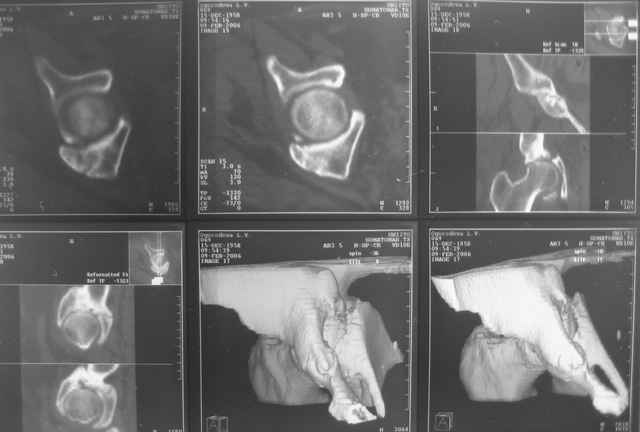

Ув.коллеги, нужен совет по представленному случаю. Пациентка 50лет. В

2003 году в результате дтп получила перелом вертлужной впадины. 1.5

месяца находилась на скелетном вытяжении, в дальнейшем до 10 месяцев

после травмы ходила без опоры на конечность. Вернулась к труду, но в

2006 году перешла на инвалидность и была поставлена в областную

очередь эндопротезирования. В данный момент уже находится в

отделении, но, судя по рентгенограммам и данным КТ, сращения на

уровне перелома не произошло. Что предпочесть?

Вложение не в текстовом формате было извлечено…

Имя     : кт-2.jpg

Тип     : image/jpeg

Размер  : 30116 байтов

Описание: отсутствует

Url     : http://weborto.net:8080/pipermail/ortho/attachments/20090324/8863a2fd/attachment-0008.jpg